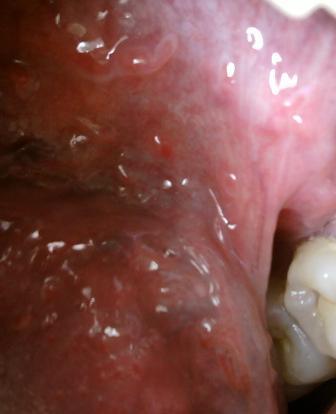

治疗尖锐湿疣比较先进的治疗方法有哪些尖锐湿疣顽疾是一种让人比较恐惧的疾病,专家在这里温馨提示:对于疾病的诊治一定要重视,相信医学,经过正规的诊治,对于疾病的治疗和康复是很关键的,希望大家对于疾病的诊治应该谨慎。

治疗尖锐湿疣比较先进的治疗方法有哪些现在随着医学水平不断进步,医学上对于尖锐湿疣顽疾的诊治也是比较重视的,专家温馨提示:要想早日治愈疾病,就应该积极接受诊治,毕竟任何疾病初期才是诊治的最佳时期,现在医学上比较常用的治疗方法有:激光疗法,微波疗法,电灼疗法和冷冻疗法等等。选择适合自身病情的治疗,方法,坚持诊治,才能更加迅速的治愈疾病。